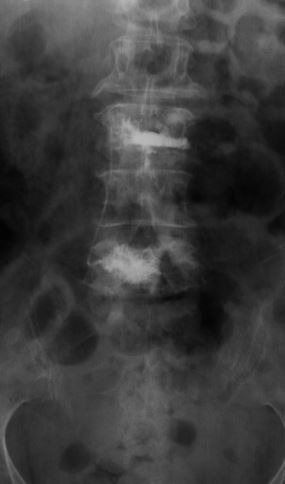

A young lady who has had previous back surgery presented to us with a new disc herniation at the same level. Her previous microdiscectomy had required an extended hospital stay because of medical complications with the patient. She had tried ample physical therapy and injections without any pain relief. She had been missing work for multiple months and was concerned she would lose her job.

She opted for the endoscopic posterolateral discectomy. Under local anesthesia [similar to dental work], the discomfort is minimized with the injected numbing medications. A small camera was placed next to the herniated disc while the patient was awake; the herniated disc was then removed. The patient felt immediate significant relief of her pain; the strength in her leg was back to normal, and she no longer felt any numbness in her legs.* She was able to go home in a few hours; about 3 months after the procedure, the patient continues to be pain free and is back to her normal activities.

Another example is a young lady who had severe low back pain. Traditionally, fusion surgery through very large incisions would be required. With the new “percutaneous” technique of placement of pedicle screws, we were able to remove her disc through her abdomen and place screws through two small incisions in her back. She is now more than 80% improved.*